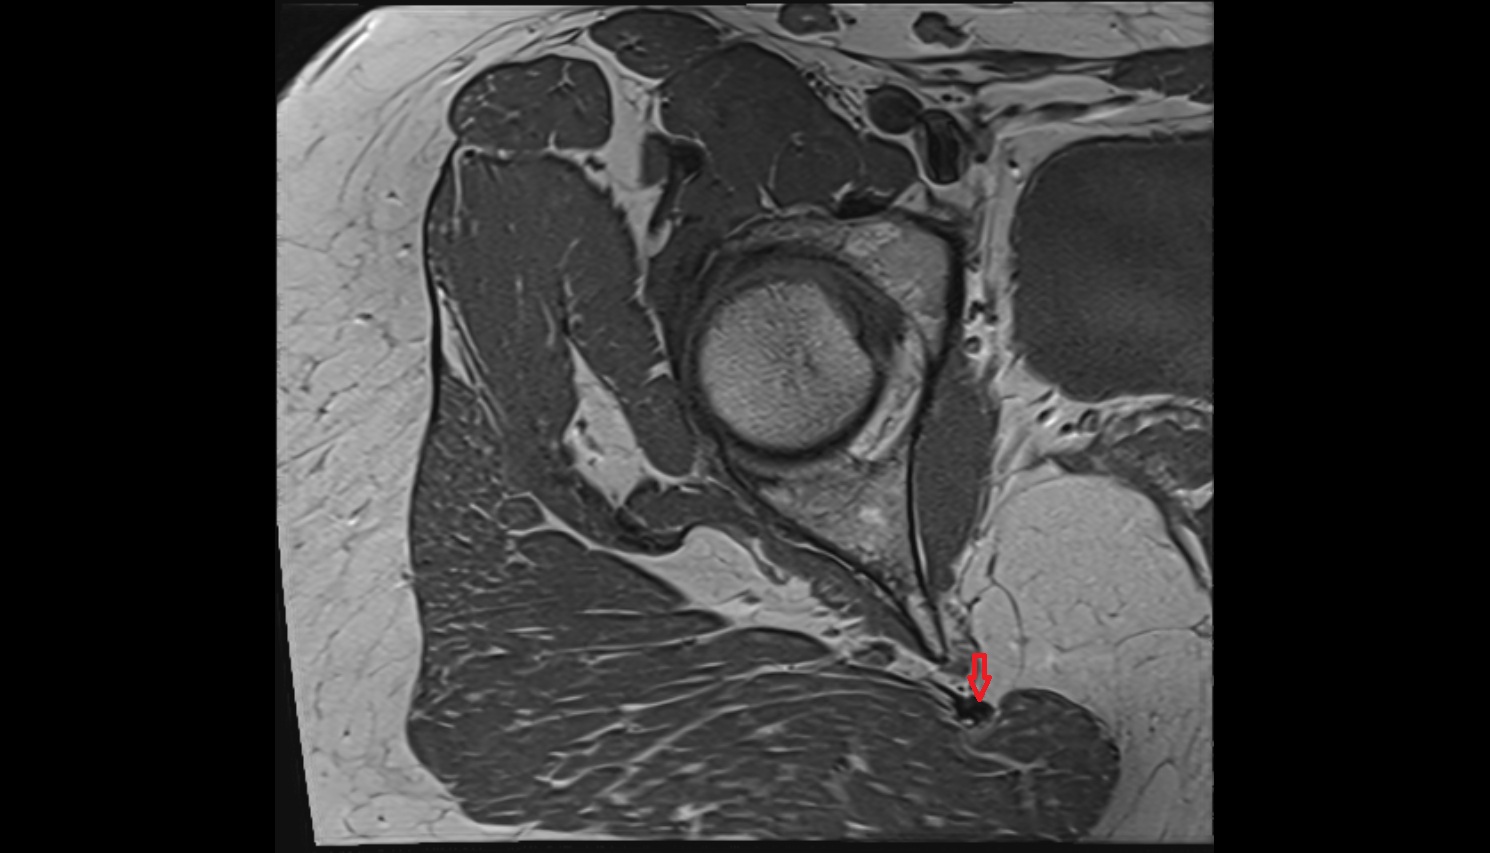

- Peripheral zone of prostate

- Anterior Fibromuscular Stroma of prostate

- Central zone of prostate

- Transitional zone of prostate

- Membranous urethra

- Prostatic urethra